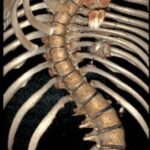

Lise öğrencisi Eren Sayın’ın, 4 yaşında kalp yetmezliği olduğu ortaya çıktı ve kalbindeki delik nedeniyle ilk ameliyatını oldu. 4 yaşında bu yana ilaç kullanan Eren, 1 yıl önce bu kez mitral kapak değişimi operasyonu geçirdi. Kalp rahatsızlığı ile birlikte skolyozu da bulunan Eren, ağrıları artından Ankara Etlik Şehir Hastanesi’ne başvurdu. Eren’in sırt bölgesinde 90, bel bölgesinde 70 dereceye ulaşan eğrilik tespit edildi. Eren, kalp kapağı ameliyatı nedeniyle kullandığı kan sulandırıcı ilaçlar kesilmeden biri 8 saat, diğeri 6 saat olmak üzere 2 seanslık riskli operasyonla skolyozdan kurtuldu. Eren, yüksek miktarda kan kaybı yaşamasına rağmen başarılı geçen operasyonun ardından sağlığına kavuştu.

Ameliyatı gerçekleştiren Etlik Şehir Hastanesi Ortopedi ve Travmatoloji Uzmanı Doç. Dr. Vedat Biçici, Eren’in kalp rahatsızlığı nedeniyle skolyozunun son dönemde hızlı ilerlediğinin tespit edildiğini söyleyerek, “Kalpteki problemlerinden dolayı riskli bir hastaydı. İlk ameliyatında ciddi kanaması olmasından dolayı ilk ameliyatını birinci seans olarak tamamlayamadan bitirmek zorunda kaldık. İmplantlarını yerleştirip, ameliyatı sonlandırdık. Genel durumu toparladıktan sonra birkaç hafta geçip, değerleri de normal değerlere geldikten sonra ikinci seans olarak tekrar ameliyata aldık. İkinci seansta omurgadaki düzeltme işlemlerini tamamlayıp operasyonumuzu bitirdik” diye konuştu.

Doç. Dr. Biçici, skolyoz cerrahisinin diğer cerrahilere göre daha riskli, daha zor olduğunu söyleyerek, “Çünkü omuriliğe çok yakın çalışmanız gerekiyor ve yerleştirdiğiniz implantlar yüzünden bazen milimetre düzeyinde yakın çalışıyorsunuz. Omurgayı düzeltirken omuriliğe hasar verme ya da omuriliğe bir problem oluşma ihtimali yüksek. Ondan dolayı riskli bir ameliyattır. Zaten cerrahi süresi uzun ve geniş bir alanda ameliyat yaptığınızdan dolayı bunlar hep riski artıran şeylerdir. Eren ayrıca kan sulandırıcı ilaç alıyor. Bunlar kesilemediğinden bu ilaçların etkisi altında ameliyata almak zorunda kaldık. Normalde bu ilaçlar ameliyat öncesinde kesilir, kanama riski azaltılır. Ama Eren’de bunu yapamadık. Bu da Eren’in ilk ameliyatta kan kaybını artırdı. İlk ameliyatta ciddi kan kaybı yaşadık, operasyonu yarıda bırakmak zorunda kaldık. Kan tablosu normal değerlere geldikten sonra ikinci seans ameliyata aldık. Onun için daha güvenli olacak şekilde iki aşamada ameliyatını tamamladık. Şu an durumu iyi. Fizik tedaviye başlayacak ve kademeli olarak normal hayatına dönecek” dedi.